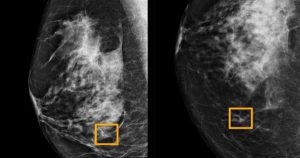

AI systém od Googlu dokáže diagnostikovat rakovinu prsu lépe než lékaři

Podle studie publikované v časopisu Nature společnost Google vyvinula systém umělé inteligence (AI), který výrazně zvýšil spolehlivost diagnostiky rakoviny prsu. AI systém od Googlu při … Pokračování textu AI systém od Googlu dokáže diagnostikovat rakovinu prsu lépe než lékaři